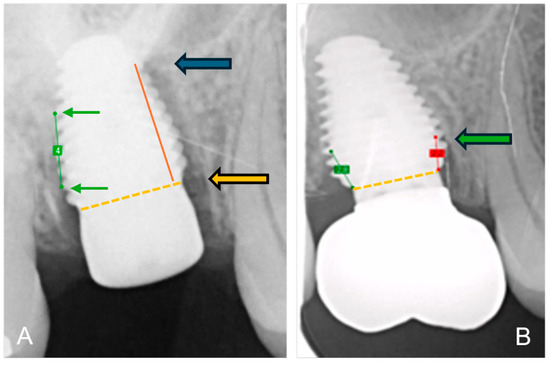

Prosthetic Management of Peri-Implant Mucositis via CRD Optimization: A Split-Mouth Case Report

Background: Subcrestally placed implants (SPIs) present advantages for bone preservation and soft tissue support but pose challenges in maintaining peri-implant soft tissue health. This case explores the role of Crest to Restoration Distance (CRD) in the development and resolution of peri-implant mucositis. Case [...] Read more.

Background: Subcrestally placed implants (SPIs) present advantages for bone preservation and soft tissue support but pose challenges in maintaining peri-implant soft tissue health. This case explores the role of Crest to Restoration Distance (CRD) in the development and resolution of peri-implant mucositis. Case Presentation: A 57-year-old woman received two SPIs—one in the upper left and one in the lower right first molar region. Despite similar implant systems and prosthetic protocols, the upper left implant developed mucositis, characterized by bleeding on probing and discomfort, while the lower right implant remained stable. Three-dimensional analysis using cone-beam computed tomography (CBCT) revealed excessive CRD at the affected site. Results: After prosthodontic revision to reduce the CRD, clinical signs of mucositis resolved, with probing depths reduced to less than 1 mm and no bleeding on probing. The control site remained healthy throughout the observation period. Practical Implications: This case highlights CRD as a modifiable prosthetic factor influencing soft tissue stability. A three-zone model—comprising the sulcus, transitional zone (TZ), and subcrestal zone (SZ)—is introduced to provide a biologically grounded framework for understanding soft tissue adaptation around SPIs. Full article

Figure 1